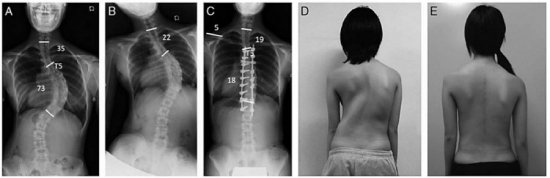

Хирург – это специалист, который занимается радикальным лечением патологий (инвазивным и малоинвазивным вмешательством). В случае когда консервативные методы лечения не оказывают результата, лечащий врач принимает решение воспользоваться услугами хирурга. При сколиозе 3 и 4 степени, когда угол искривления больше 50 градусов, происходит деформирование, при котором нарушается работа внутренних органов.

Человек испытывает сильную боль, у него меняется походка и происходит асимметрическое искривление всего тела. В таком случае лечащий врач решает, какой из методов хирургического вмешательства будет проводиться: инвазивный или малоинвазивный. При инвазивном вмешательстве операция проводиться непосредственно на позвоночном столбе, где хирург располагает металлические пластины. Эти пластины корректируют позвоночник и восстанавливают нормальную осанку.

Хирург устанавливает подвижные и неподвижные металлические пластины в тех местах, где необходима коррекция позвоночного столба. Это позволяет пациенту спокойно передвигаться, наклоняться и сгибаться после реабилитационного периода

Хирургическое вмешательство

Самым эффективным методом оперативного лечения сколиоза врачи считают установку в пораженной области спины удерживающих металлических пластин. Во время процедуры хирургом выполняются действия, направленные на изменение положения позвонков и их последующей правильной фиксации с использованием специальных штырей. Через 1 или 2 года проводится операция по изъятию металлических пластин.

Несмотря на радикальность, такой способ является наиболее эффективным на запущенных стадиях сколиоза. Но при наличии располагающих факторов спина может деформироваться снова. Поэтому крайне важно даже после выздоровления всегда правильно держать осанку, регулярно заниматься лечебной физкультурой и посещать массажные салоны.